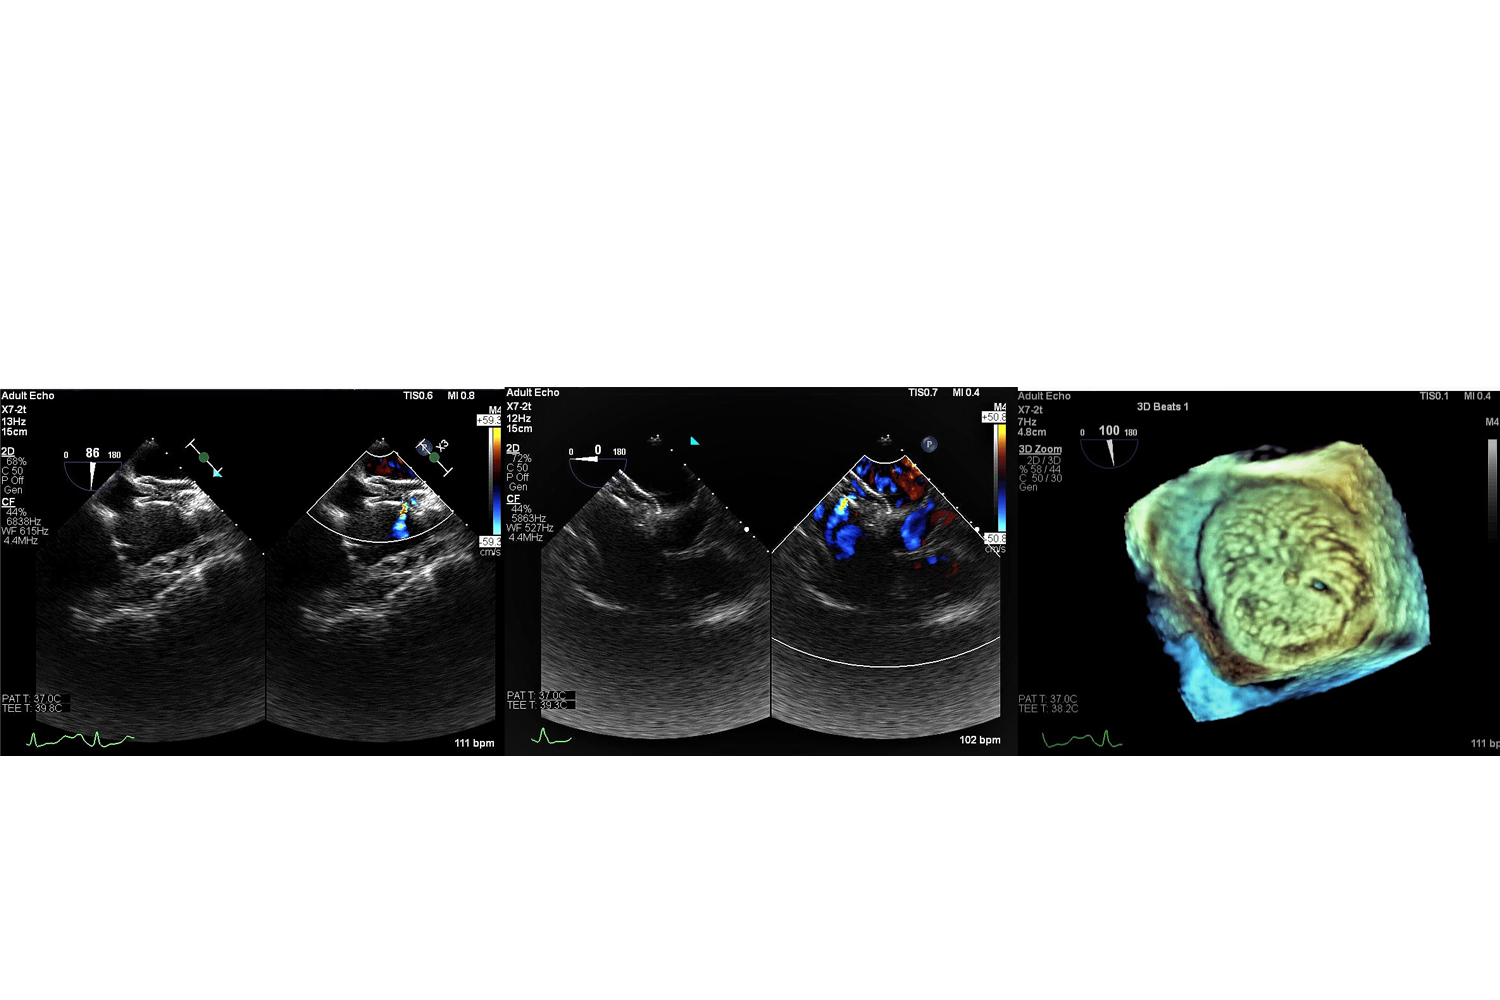

Image of the Week - 7 May 2025

6 May 2025

Doctor Nicola Amelotti

Doctor Albert Teis Soley

Doctor Victoria Delgado